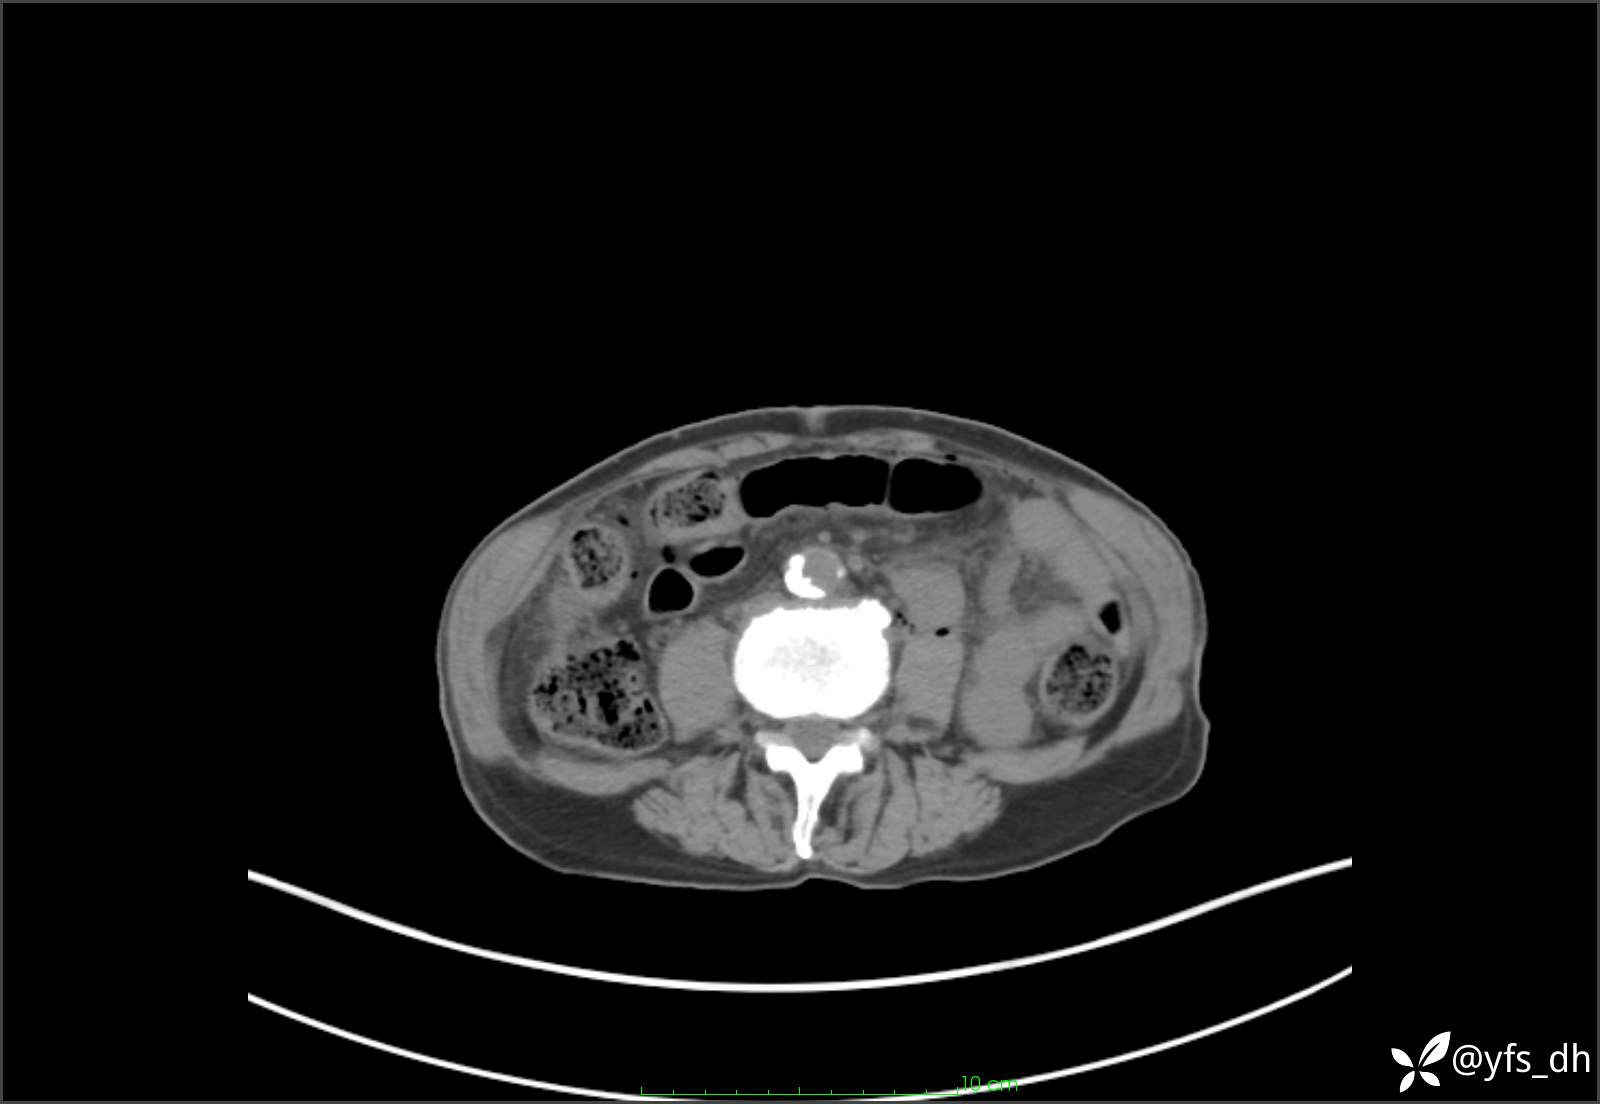

1.简要病史:患者4天前突发上腹部疼痛不适,但可以忍受。3小时前饭后突然加重,不能忍受后就诊。

2.简要手术记录:术中见腹盆腔大量肠液及粪便,乙状结肠中下段见一约3cm的破口。